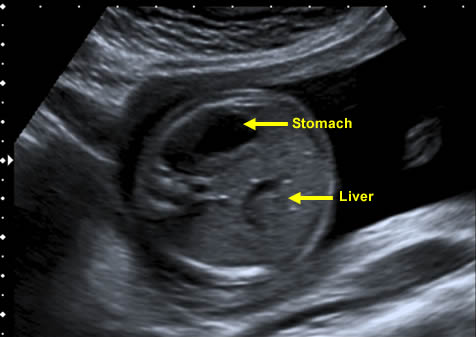

The fetal liver is the largest organ of the abdomen. It is responsible for glycogen storage – essential for continued fetal growth. If the nutrition of the fetus is diminished, most of the available nutrition for growth is diverted to protect the development of the brain.

If there is inadequate nutrition, then storage within the liver diminishes and growth of liver and therefore of the abdomen slows or, in severe growth retardation, stops. This is the 'head sparing' effect. It means that to detect a poorly growing fetus, measurement of the abdomen is essential.